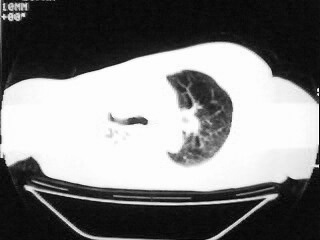

以下是引用随光逐影在2009-2-10 0:07:00的发言:[br]1)右肺放射性肺炎并节段性肺不张?请结合相关病史。2)右侧胸膜肥厚、粘连。3)心包膜增厚(或心包少量积液)。